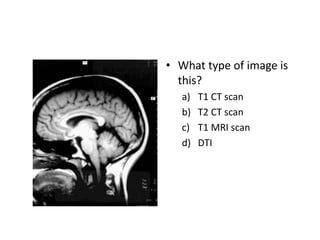

• What type of image is

this?

a) T1 CT scan

b) T2 CT scan

c) T1 MRI scan

d) DTI

T1/T2 are subsets of MRI

scans.

T(wh)one, white matter is

white.